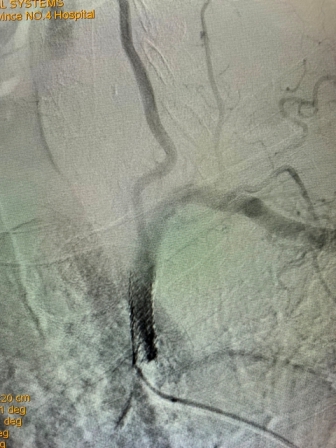

该患者是一位79岁老年男性,门诊以“头晕伴走路不稳”主诉入院。既往有高血压、冠心病PCT术后、慢阻肺病史。入院后完善相关检查,行B超检查考虑“左侧锁骨下动脉盗血”,进一步检查DSA全脑血管造影术时发现:“左侧锁骨下动脉闭塞,左侧锁骨下动脉盗血”。为解决患者疾病痛苦及改善其生活质量,神经内科任主任刘蔚玲主持召集专家团队讨论并精心安排,在客座教授刘亚民周密指导下,由神经内科侯有荣副主任医师、孟军鹏主治医师、赵荣健等骨干医生,通过开通闭塞处血管、球囊扩张后置入支架,手术顺利,术后造影显示患者左侧锁骨下动脉血流再通,锁骨下动脉盗血现象消失,血管再开通,患者术后无明显不适、后循环缺血症状消失。手术极大地改善了其生活质量,同时也有效地预防了严重的脑卒中事件的发生。

(术前造影) (手术后造影)

此例高龄患者、锁骨下动脉闭塞后再通、同时联合椎动脉狭窄病变的同期治疗,其手术复杂、难度大、风险高,神经介入手术创伤小,恢复快,效果立竿见影,其闭塞血管的顺利开通为预防其以后再发生脑梗死奠定了极为重要的基础。该例手术成功完成,再次标志着亚色视频 神经内科(卒中中心)神经介入技术水平更上一层新台阶。(采编 党委宣传部)